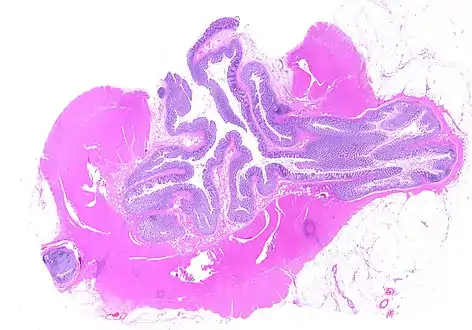

CT scan showing extensive diverticulosis of the sigmoid colon

Diverticular disease

Whole slide of a transverse section of the left colon with diverticulosis

Diverticulosis is defined by the presence of multiple pouches (diverticula) in the colon.[22] In people without symptoms, these are usually found incidentally during other investigations.